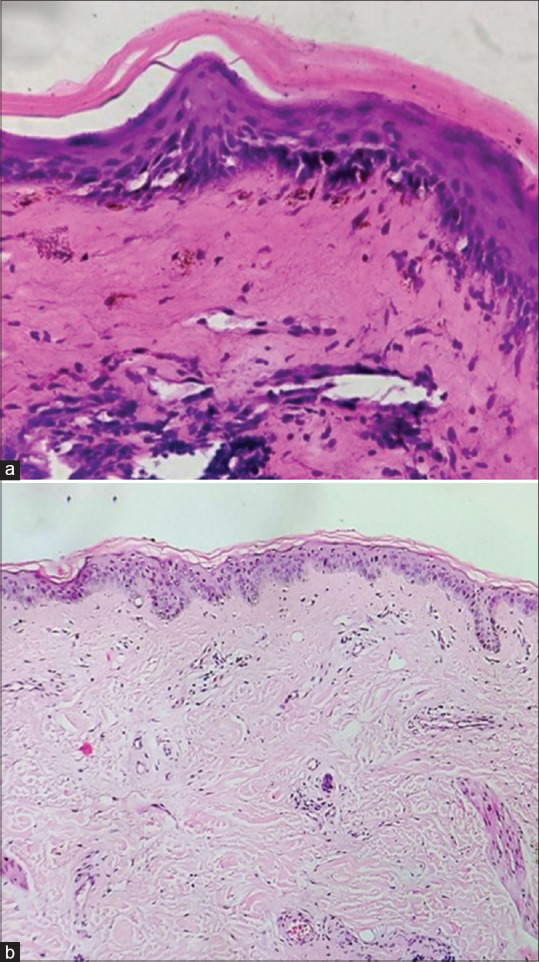

Parry-Romberg Syndrome with Localized Plaque Morphea and Localized Discoid Lupus Erythematosus: A Case Report of a Rare Overlap.